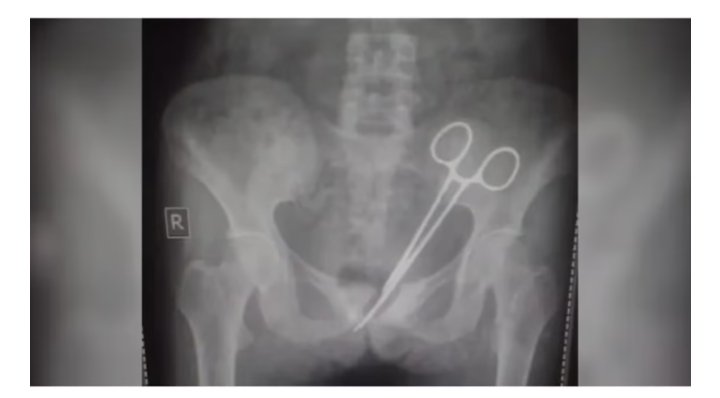

കത്രിക വയറ്റിൽ കുടുങ്ങിയ സംഭവം ; ഡോക്ടർക്ക് വീഴ്ച സംഭവിച്ചിട്ടില്ലെന്ന് അന്വേഷണ സമിതിയുടെ വിലയിരുത്തൽ

തിരുവനന്തപുരം : കത്രിക വയറ്റിൽ കുടുങ്ങിയ വണ്ടാനം മെഡിക്കൽ കോളേജിലെ ചികിത്സാ പിഴവിൽ ഡോക്ടർക്ക് വീഴ്ച സംഭവിച്ചിട്ടില്ലെന്ന് അന്വേഷണ സമിതിയുടെ…